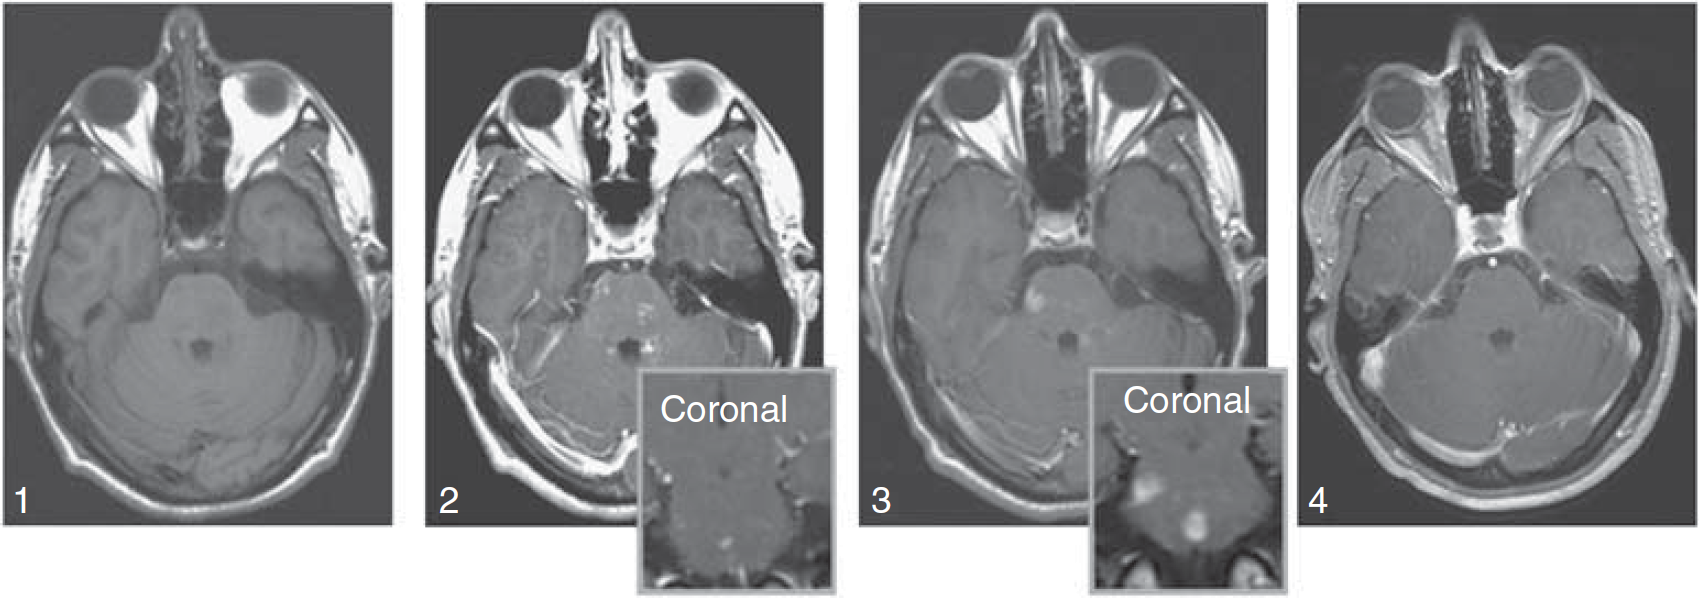

Patient with ADEM. Axial, T1-weighted images without (1), and with (2) gadolinium (inset, coronal) show faint, subtle enhancement in multiple brain stem lesions. Six days later, significant and more prominent enhancement can be seen at the same sites (3) using ferumoxtran-10 (inset, coronal). Three months later, the lesions no longer enhance on T1-weighted images with gadolinium (4).